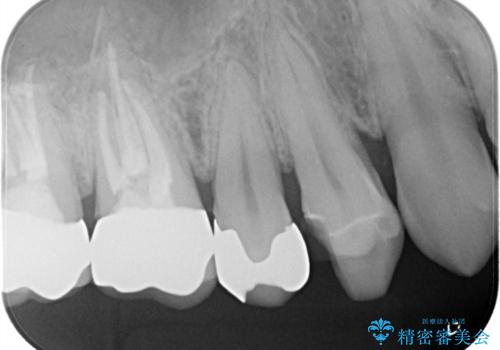

他院のセラミックインレー やり直し治療

- 以前、他院で入れたセラミックインレーが欠けてしまっているとのことでご来院されました。内部に虫歯が無いかどうか確認したうえで、割れにくいように形を工夫して新しいセラミックインレーをセットしました。術後の経過は良好です。

セラミック自体が薄すぎる場合や、十分な厚みがある場合でも局所的に強い力がかかるとセラミックは割れてしまいます。今回の患者様のセラミックが欠けてしまった要因は、おそらく歯並びの問題で、その歯に日常的に過剰な力がかかっていたためだと予想されます。割れたセラミック自体は基本的につなぎ合わせられないため、作り直しになります。今後同じことが起こらないようにするために、根本的に歯列矯正を検討しても良いかもしれません。